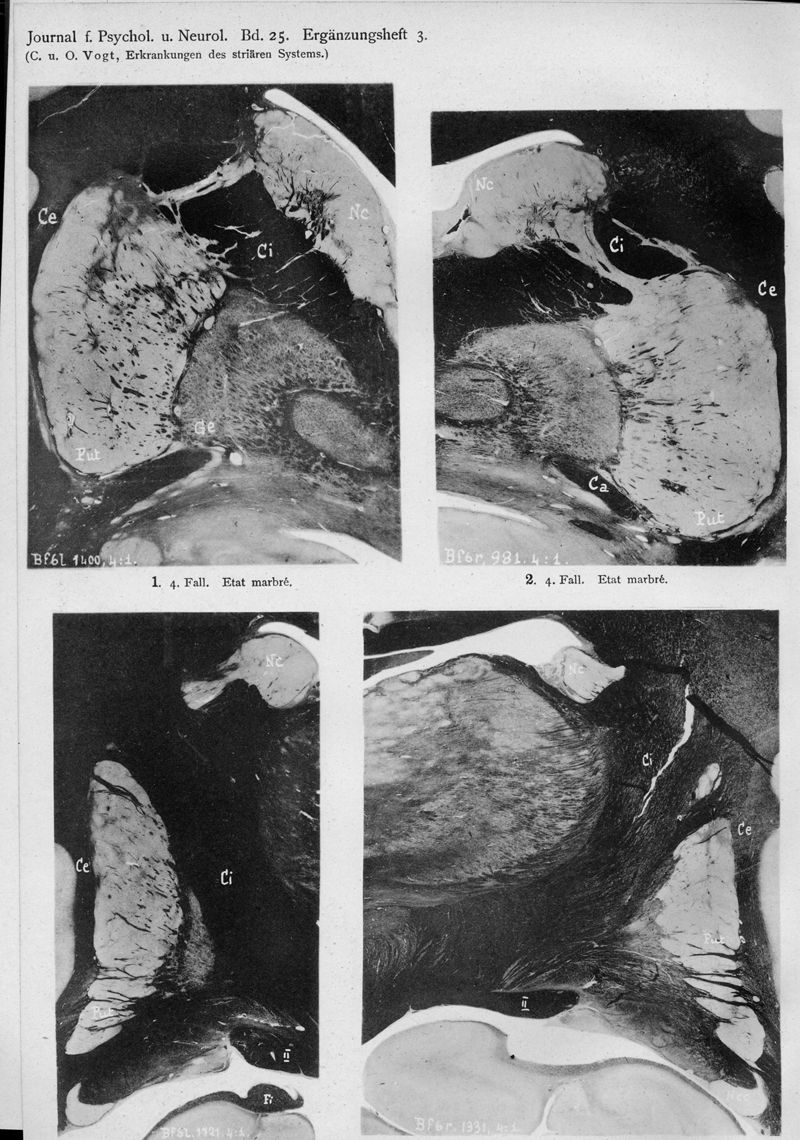

VOGT, Cécile / VOGT, O.

In : Journal für Psychologie und Neurologie,

1920, Vol. 25, pp. 627-846